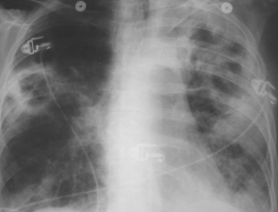

<p>A 48-year-old woman with a 50-pack year smoking history presented with worsening dyspnea and progressive weight loss of 25 lb over the previous 4 months. In addition, she had a...

10/05/2011